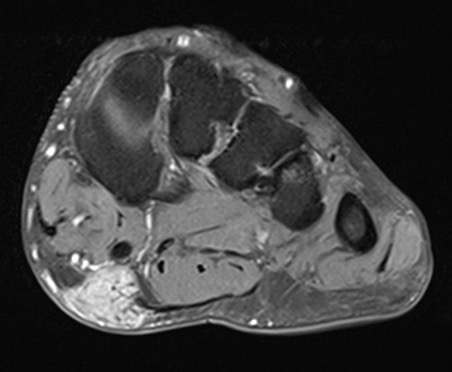

MRI

Focal oval shaped lesions within the plantar fascia